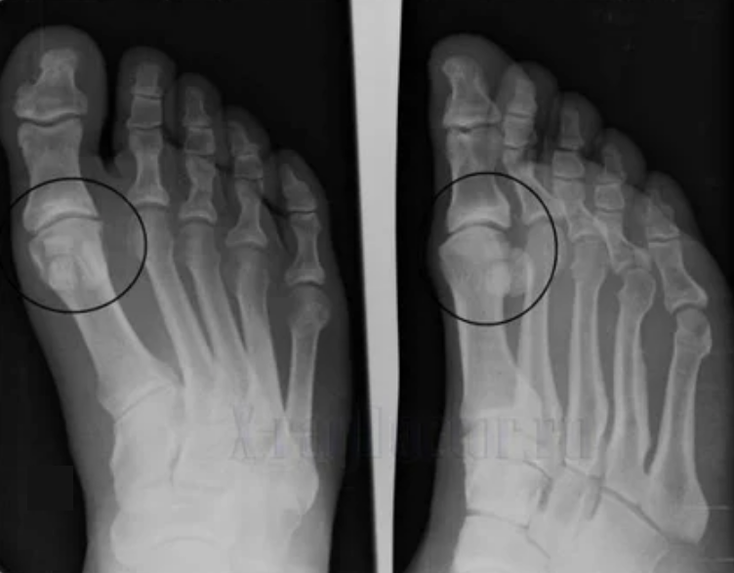

To make a diagnosis, rheumatologists study the patient's complaints and prescribe an X -Ray exam.Most of the time, the radiography is used in 2 projections.The doctor analyzes the presence of distribution disorders in the hyaline cartilage and bone joints.If the joint gap is reduced, the bones are delayed or flattened, there are cystic formations on the cartilage surface, osteophytes are obvious signs of osteoarthritis.During the inspection, osteoarthritis indicates the instability of the articulation: the axis of the limbs and the subluxation is altered.

Often, an X -ray image cannot give complete information about the condition of the joint.For a more thorough study, computerized tomography is prescribed, it is effective to examine the bones.Magnetic resonance is more frequently used to study soft tissues.